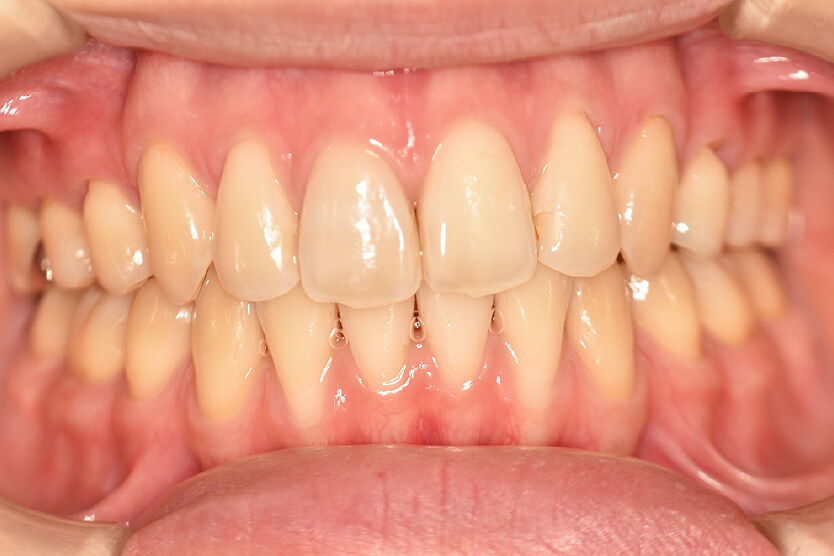

動的治療終了時

症例 症例 症例 症例

治療としては、上下左右第一小臼歯を抜歯して、セルフライゲーションブラケット装置(デーモンシステム)とマウスピース型矯正装置(インビザライン)で配列を行いました。

この際、上顎に歯科矯正用アンカースクリューを設置し上顎前歯部後退時の土台としました。

開咬については、顎間ゴムの協力もあり改善されました。

治療期間としては、2年1か月でした。